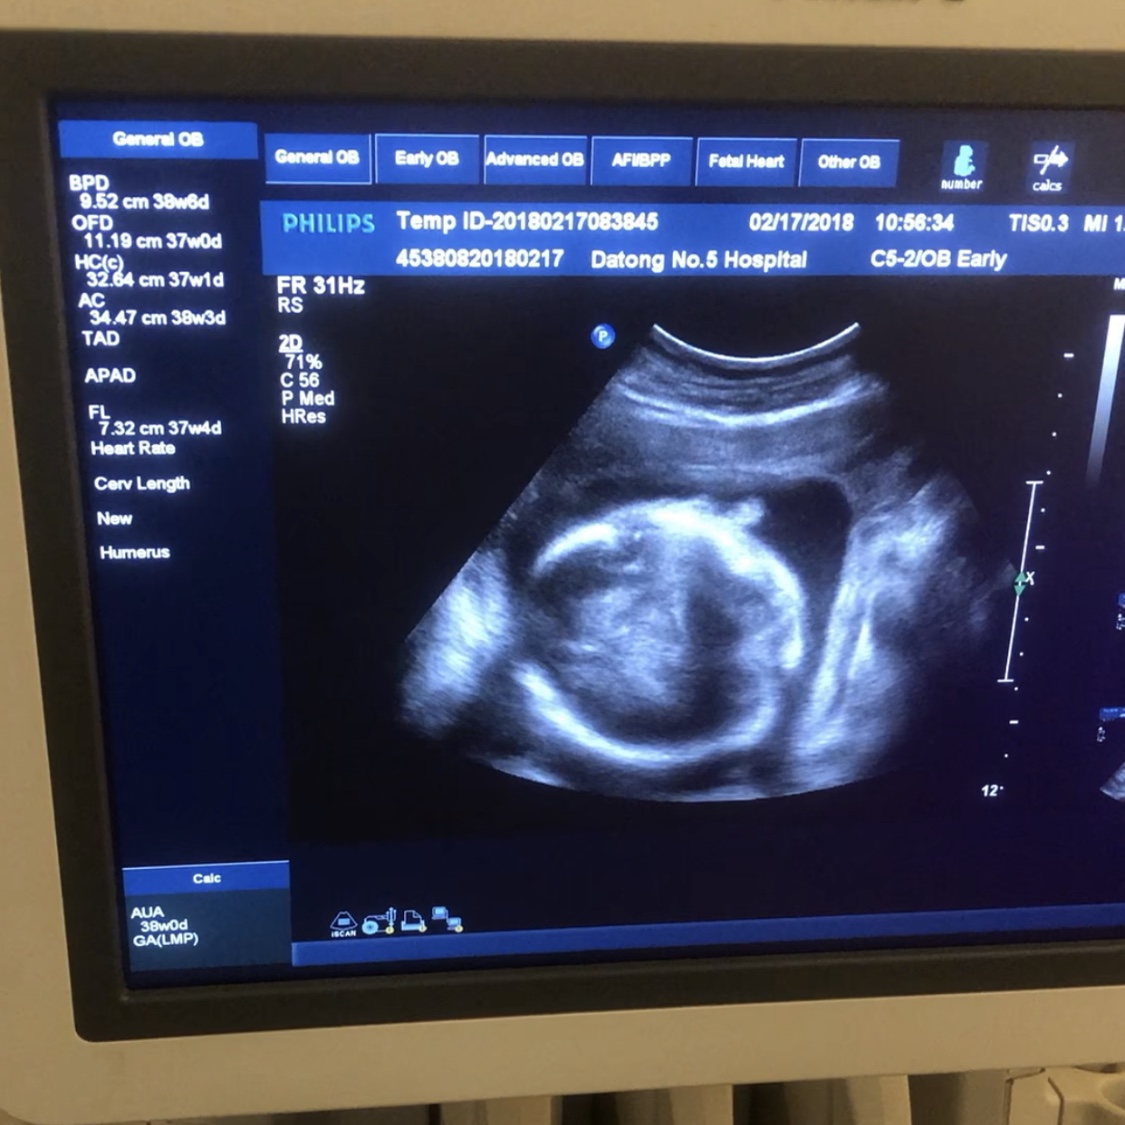

5.疫情期间孕妇要按时产检吗?

孕妇如无特殊情况可与产科医师协商适当延后产检时间,字形俱佳检测胎儿宫内情况(胎动)。必须产检时,应提前预约,做好防护,并尽量缩短就医时间。孕期出现异常情况(视物不清、心慌气短、血压升高、阴道出血或有褐色分泌物、异常腹痛、胎动异常等)应及时就医。不要因恐惧、担忧延误就医。